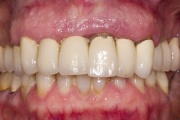

Parodontiit

Luukadu agressiivse parodontiidiga patsiendil